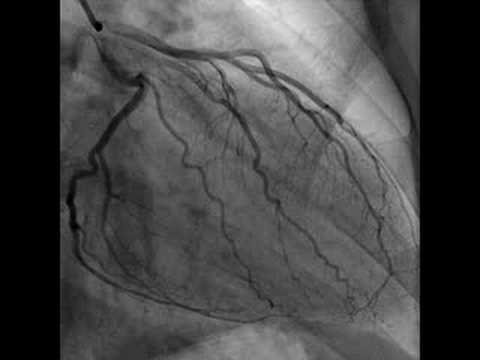

Рука после коронографии

Рука после коронографии 111 фотографий